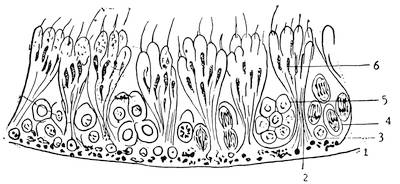

Structure of testicles.—The testicle is covered with a thick, white, fibrous coat, the tunica albuginea. This tunica sends off about 200 to 400 septa or trabeculae testis. These trabeculae31 divide the parenchymatous tissue of the testicle into numerous conical lobules, and, converging towards the posterior margin of the testicle, form a solid fibrous mass, the so-called corpus Highmori.

The parenchymatous tissue of the testicles consists of numerous fine tubules, the canaliculi seminiferi. Each lobule contains a number of these fine tubules. In the beginning and through their entire course the seminal tubules or canaliculi are tortuous; towards their ends, however, they become straight. When they reach the corpus Highmori, the thickened, enlarged part of the tunica albuginea, they collect and unite, to form a network, the rete vasculosum. This rete sends off 12 to 14 large tubules, the vasa efferentia, which, running in a straight line, pass the corpus Highmori and enter the epididymis. The corpus Highmori serves as a point of entrance for the arteries and nerves and as an exit for the veins of the testicles.